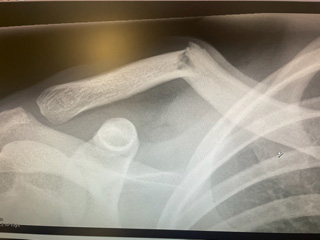

Just thirteen days before the beginning of the archery season, my son wrecked on his dirt bike breaking his collar bone and fracturing his scapula in three places. Since Carson was the only Utah archery tag holder, it seemed as if the hunt was over even before it started.